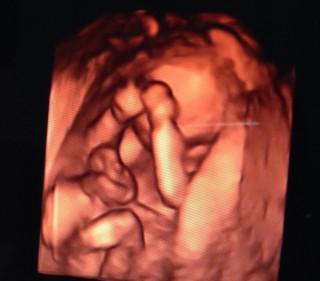

いつも検診時に撮って貰えるのが、脚の写真! 立派!と感動です!!!!どんどん、人間らしくなっていってくれるので、成長が楽しいです! その先に♪男の子の証がございました!!

性別がはっきり分かった記念すべき一枚です!

三人目で初めての4D(*^^*)お兄ちゃん、お姉ちゃんと鼻と口がそっくりです!! いっぱい動いて元気でした♪右手が「GJ!」しています。